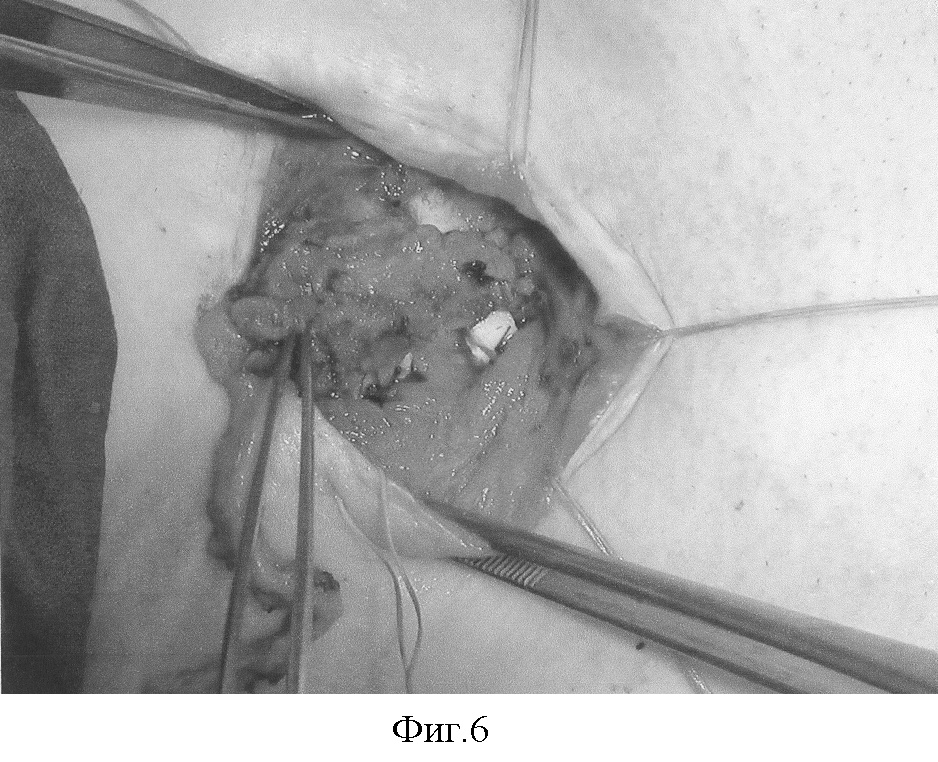

Фиг.1 – мягкие ткани по краям дефекта передней стенки трахеи мобилизованы. Этап установки стента в просвет трахеи.